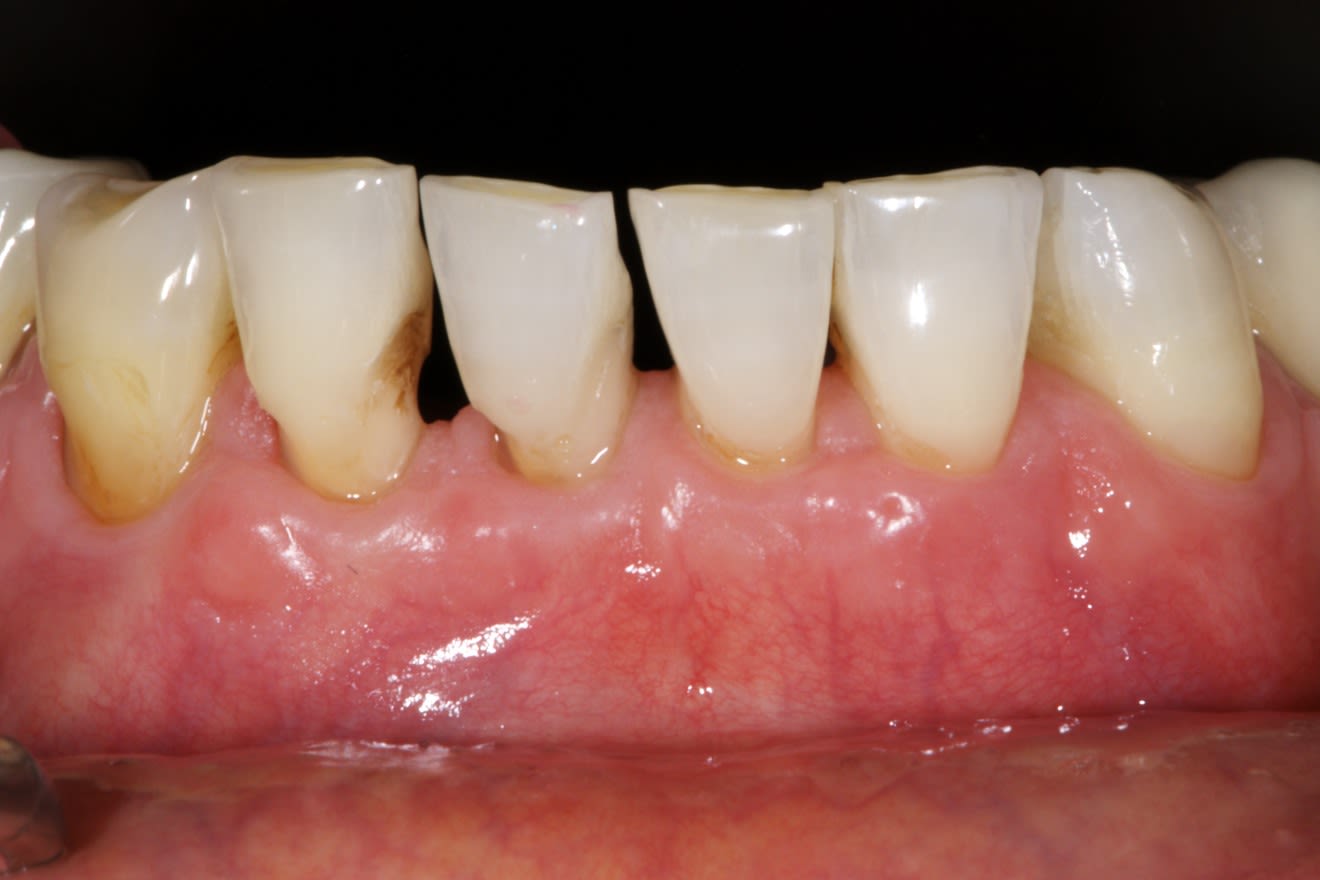

Résultat sympa à 14 jours

Cependant ici l'indication aurait plus été une technique avec une greffe épthélio-conjonctive en 1 ou 2 temps amha.

Car même si l'épaisseur de gencive attachée est plus importante que sa hauteur, ici c'est trop limite.

Une récidive sur 31m et 32m, voir 41m est à prévoir.

Pas d'accord avec toi pour la GEC

GEC dans un tissu mince comme ça c'est pas mieux, et doit faire du 2 temps, avec un résultat moche esthétiquement.

Récidive ??? non, au contraire, ça sera encore plus beau dans qq mois. Le biotype change avec l'ajout d'un tissu autogène dense comme celui utilisé. Je trouve pas ça limite du tout.